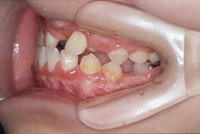

反対咬合と前歯が生えてこない事を主訴に来院された、10歳4か月の男の子です。診断「下顎骨の過成長による骨格性反対咬合で上顎正中の左方偏位と埋伏歯を伴う」1期治療で反対咬合の解消と埋まっていた前歯を牽引しました。